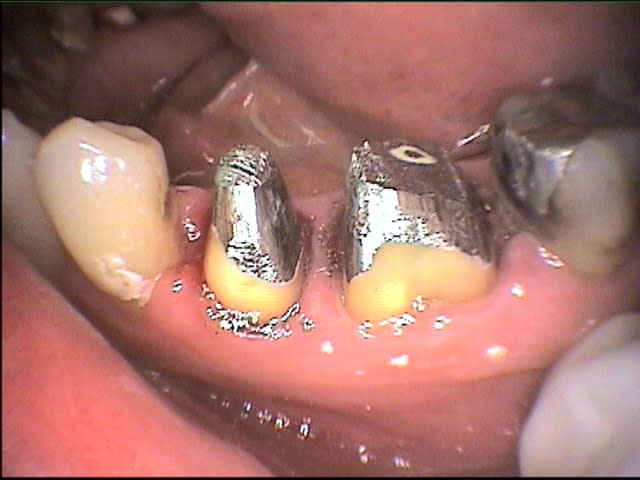

conversion des images de cyber en JPEG:

1ju0 lmt2bb - Eugenol

001ls8 xc8lt8 - Eugenol

003fp3 dsnpbv - Eugenol

2sf0 zc2jod - Eugenol